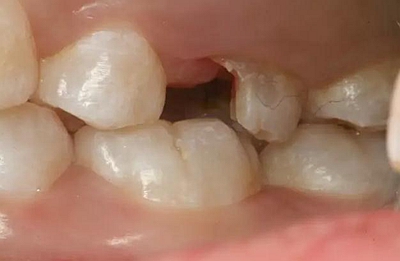

病例一 女性,20歲,大學生,要求補牙,檢查口內可見A6大面積缺損,近中牙齦息肉,拍X片,根管充填物略差,但根周未見明顯陰影,口內檢查無叩痛。建議患者冠延長手術+高嵌體修復。

患牙遠中邊緣嵴完整,強度沒有降低,故擬保留遠中邊緣嵴,高嵌體修復。首先去除腐質及原墊底材料,流體樹脂+3M Z350XT樹脂墊底。局麻下行冠延長手術。在此需要提及個人的一個觀點。冠延長手術原則上要求3-6個月以上才能永久修復。但是個人喜歡后牙肩臺建立在齦上,所以修復后的修復體邊緣位于牙齦上方1mm,對牙周的愈合影響較?。ㄈ绻麨辇l下邊緣則要慎重),故該患者術中按照齦上邊緣的設計進行冠延長手術。以下為術中: